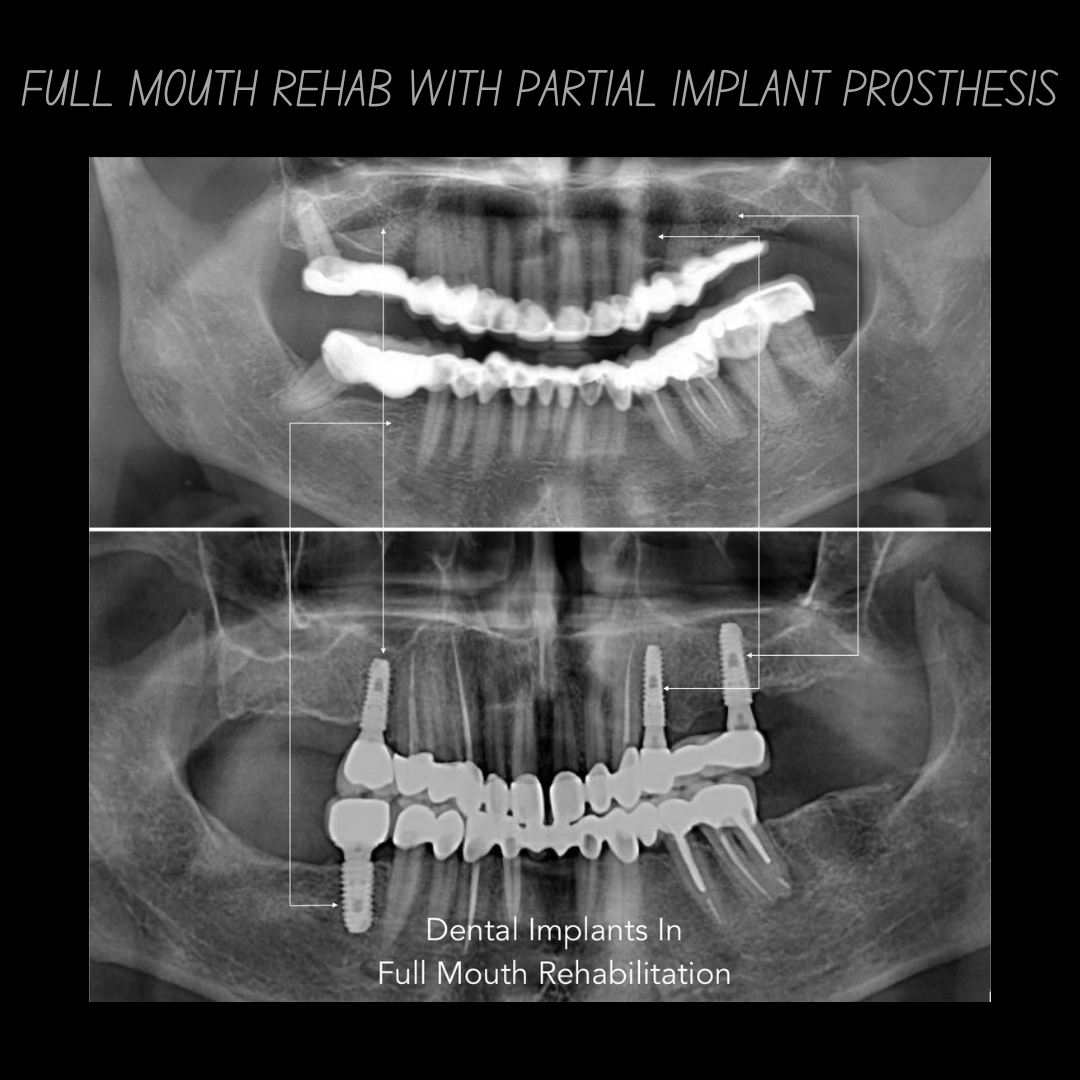

Dental implants are artificial tooth roots made of biocompatible titanium placed into the jawbone to replace missing teeth. They function like natural teeth and provide a strong foundation for crowns or bridges.

Our clinic uses advanced digital implant dentistry, guided by one of Pune's top expert dentists, including CBCT 3D scans, intraoral scanners, and precision-guided planning to ensure accurate implant placement, faster healing, and predictable results.

| All-on-4 (per arch) | ₹1,50,000 – ₹3,50,000 |

| All-on-6 (per arch) | ₹2,00,000 – ₹4,50,000 |